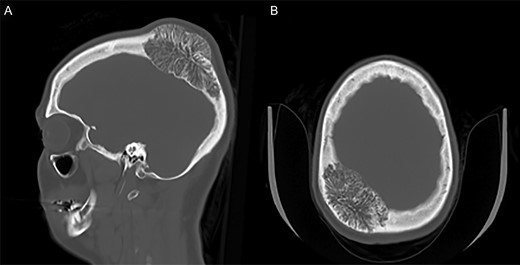

CT scans showed a 6.4 cm × 6.4 cm × 4 cm right parietal calvarial mass (Fig. 1) with expansion of the diploic space and mass effect on the right parietal lobe.

CT bone window with sagittal (A) and axial (B) views provided. A large right parietal calvarial mass expanding into the diploic space and exerting mass effect on the right parietal lobe is demonstrated.